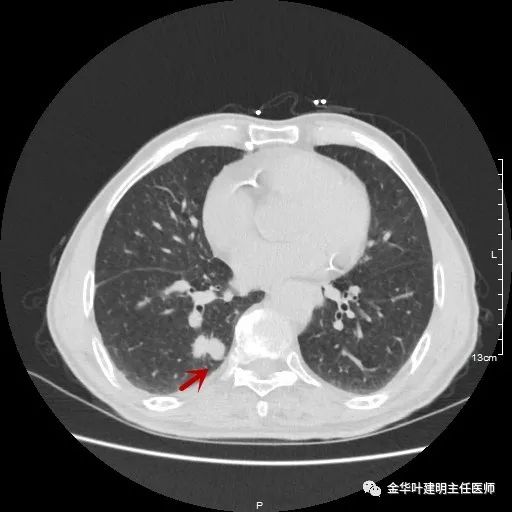

以上示右下叶病灶5。也是主病灶,是实性块状分叶的占位性病变,基本可以肯定是肺癌。单病灶看需下叶切除并清扫淋巴结。

以上示右下叶病灶6。同样是囊腔型病灶,但较前几个范围小,可囊壁同样为磨玻璃影,也是较为典型的囊腔型肺癌表现,单灶来看可下叶背段切除。